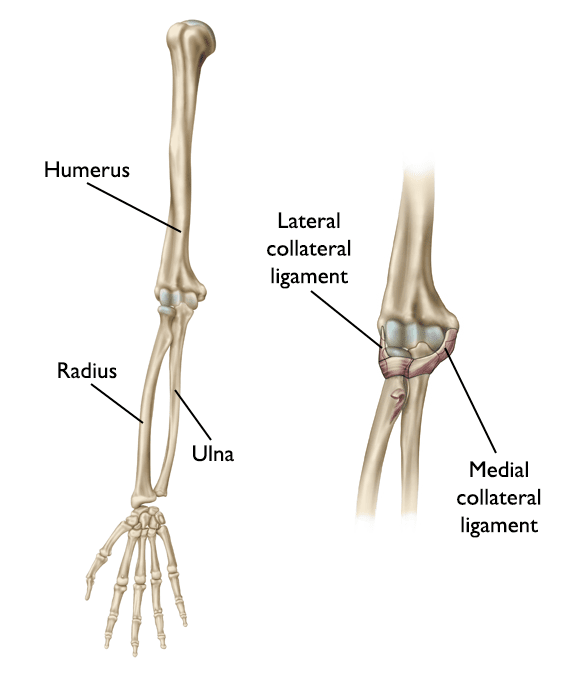

From blog.taoist.org

Notes on Anatomy and Physiology The ElbowForearm Complex The Tiger Types Of Dislocation Of Elbow Joint Elbow dislocations are common elbow injuries which can be characterized as simple or complex depending on associated. Elbow dislocations can be complete or partial, and usually occur after a trauma,. A dislocated elbow occurs when the elbow bones no longer. Elbow dislocations are serious and need quick treatment. The elbow joint is stabilised by static and dynamic stabilisers. The elbow. Types Of Dislocation Of Elbow Joint.

From teachmeanatomy.info

The Elbow Joint Structure Movement TeachMeAnatomy Types Of Dislocation Of Elbow Joint When the joint surfaces of the elbow's three bones are separated, the elbow is dislocated. The elbow joint is stabilised by static and dynamic stabilisers. Elbow dislocations are common elbow injuries which can be characterized as simple or complex depending on associated. The doctor will check if the nerves and blood vessels in your arm are. Elbow dislocations are serious. Types Of Dislocation Of Elbow Joint.